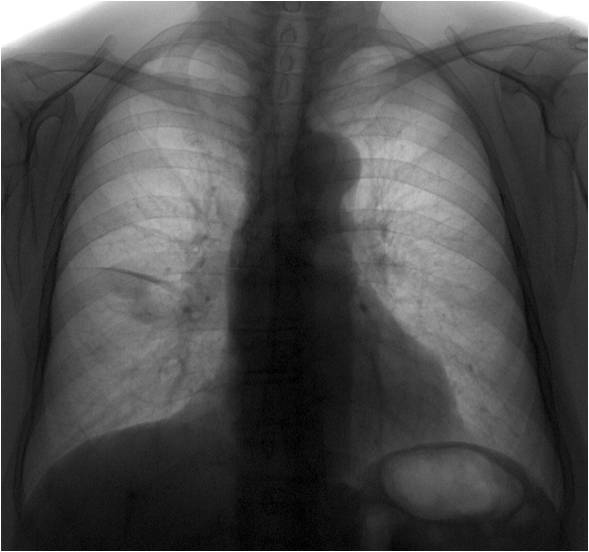

Жалоб у этой женщины 1939 года рождения нет. При плановой ФГ выявлены изменения. Поднят архив за 2009 год (из анамнеза - в 2009 году кашляла около 1,5 мес)

Принесли диск с ФГ на консультацию; вызвал на дообследование и выполнил правый бокой снимок.

На боковой рентгенограмме явственное утолщение междолевой плевры в главной и малой междолевых щелях. Возможно наличие некоторого количества выпота - черные стрелки в малой междолевой щели.

Конечно, и на прямом снимке четко определяется "плевральная" компонента - малая междолевая щель и "легочная" компонента, в виде локального снижения прозрачности легочной ткани.

И в довершении, анализируя, первый снимок, где отсутствуют и "плевральная и легочная" компоненты, а присутсвует симптом локального усиления и обогащения легочного рисунка, я предположу локальный воспалительный процесс, возможно даже менее субсегментарного, который имел место быть в средней доле правого лёгкого, возможно, у "теневой развилки" главной и малой междолевых щелей.

Согласен, что в 2009 году имело место субсегментарное воспаление у развилки междолевых щелей, что, в итоге, вылилось в развитие междолевого осумкованого плеврита по ходу горизонтальной междолевой щели (его то как раз и недостает на страницу о плевритах, правда случай, возможно, не столь показателен). Слчучай на контроле. После консультации обл.пульмолнолога будет, я надеюсь, проведен курс лечения...а там посмотрим.